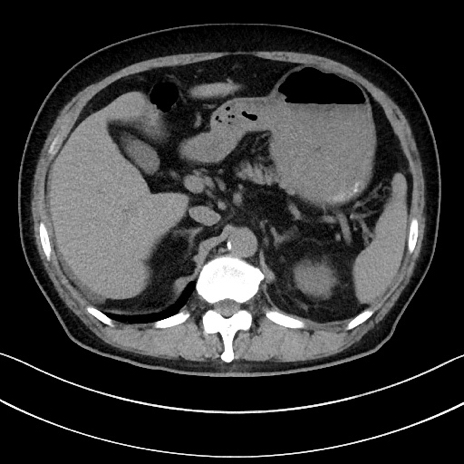

冠状断像

【症例】70歳代男性

【主訴】腹痛

【現病歴】今朝から腹痛あり。全体的に痛い。特に左上の方。排ガスが今日はない。冷や汗が出る。

【既往歴】直腸癌術後

【身体所見】左側腹部〜上腹部に圧痛あり。腹膜刺激症状明らかなではない。軽度反跳痛。左下腹部に術後瘢痕あり。

【データ】WBC 7700、CRP 0.02